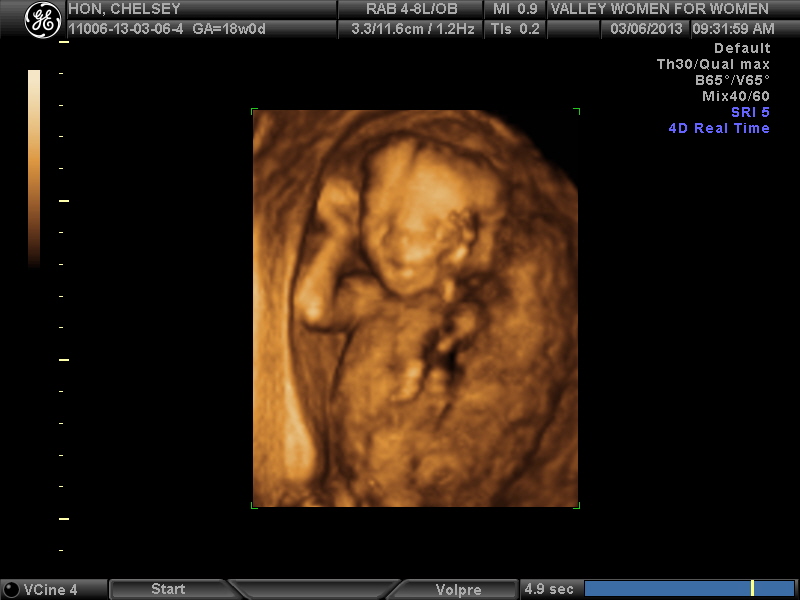

I am so stinking excited!! Lucky for me, the days just before the ultrasound went really quickly so I wasn't waiting in agony. Wednesday morning my appointment was at 9:10. Spencer and I got up at like 7:30, he made french toast (you have no idea how big of a deal this is. I had been waiting to eat these amazing strawberries I had on french toast since like Sunday. It was terrible!), and we headed out to the doctor. We had a short wait and they took us back. The ultrasound was so fun. I know it was pretty much the same as every other one, but it is so fun seeing our little baby on the screen. It is also fun because she is a lot farther up now and closer to my tummy so the technician didn't have to push very hard to see her :). She checked the spine, the kidneys, the bladder, the brain, the length of the bones in her legs, the heart (that part was really cool. You could see all 4 chambers and could see them moving....crazy!!), and measured the heart rate. After all of this she tried to find out the gender. Our little lady decided she didn't really want to open her legs (I guess I should be happy about that, but it made it quite frustrating!) After a little bit, the technician had me roll on my side to try and get the baby to move. Shortly afterwards she started to cooperate. The picture was finally clear enough and the technician said, "It's a girl". I was so happy! I have been thinking it was a girl the whole time!! And so had everyone else. It would have been a sad day if everyone and their dog had been wrong; even though I would have loved him either way if it was a boy. She finished up the ultrasound, printed some pictures, and gave us a disc of all of the pictures from the entire ultrasound. This is really nice because now the pictures will be perfect and clear, not blurry and off color.

It's crazy to see how much she looks like a human just from the past 6 weeks. You can see her little face and her fully developed arms :).